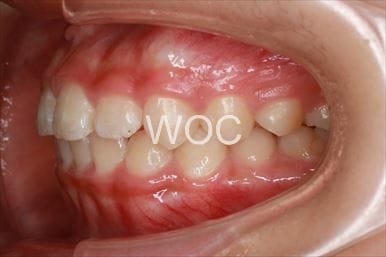

出っ歯舌側矯正

上下舌側矯正を希望。

通院状況や歯みがきの協力が良かったため、1年7ヶ月で治療を終えることができました。※装置と注意事項に関しては、大人の矯正装置一覧へ。

- 年齢:20歳女性

- 主訴:出っ歯が気になる

- 基本矯正料金:120万円

- 治療期間:1年7ヶ月

- 抜歯部位:上顎両側第一小臼歯